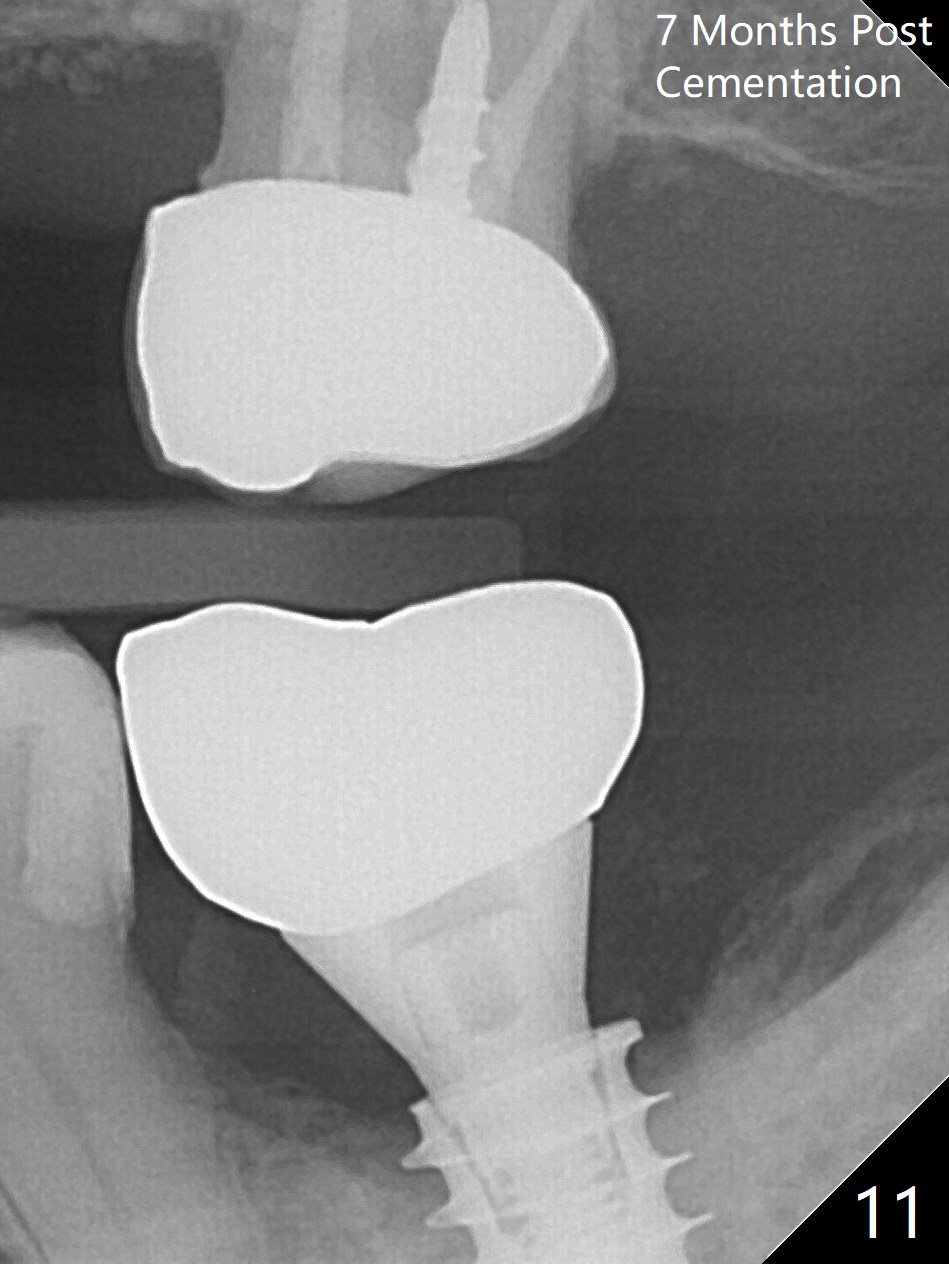

There is no apparent bone loss 4 months postop (Fig.10).  There is chewing pain in spite of occlusal adjustment 7 months post cementation (Fig.11-13: increased radiolucency around the implant).  The crown/abutment is removed and a healing abutment is placed (6x3 mm); the implant is stable.  The patient return for re-evaluation in 3 months (15 months postop); radiolucency appears to reduce (Fig.14).  But there is pain when the healing abutment is being removed.  After local anesthesia, the implant is removed with a wrench.  Following debridement of the osteototomy (intact, although tender), a 5x10 mm dummy implant with SLA surface is placed (Fig.15).  After 5.5 mm tap, a 5.5x8.5 mm implant is placed with >50 Ncm (Fig.16).  A 6.8x5 mm healing abutment is placed, followed by periodontal dressing.  Re-analysis of preop CBCT shows that the bone density at the site is low: 70 units average.  Progressive loading is necessary for this case 4-6 months postop.  The soft and hard tissues around the implant seem to heal 4 months postop (Fig.17).